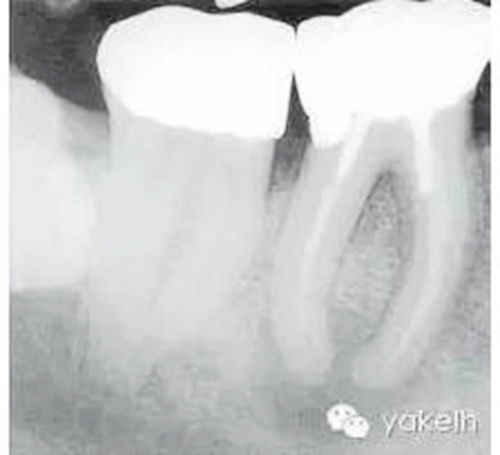

根尖X線片顯示什么(圖5.1.1)?

圖5.1.146術(shù)前X線片,顯示金屬冠修復(fù),每個牙根內(nèi)均有金屬樁,根管充填物均短于放射學(xué)根尖且有根尖周透射影。

金屬冠修復(fù)。

近遠中牙根內(nèi)均有金屬樁。

在近中根內(nèi),樁的尖端向根管側(cè)壁偏移。

近遠中牙根均有中度彎曲。

近遠中根管充填物均短于放射學(xué)根尖。

近遠中根尖周均有明顯的透射影。

右下頜第三磨牙(48)緊靠右下頜第二磨牙(47)遠中。